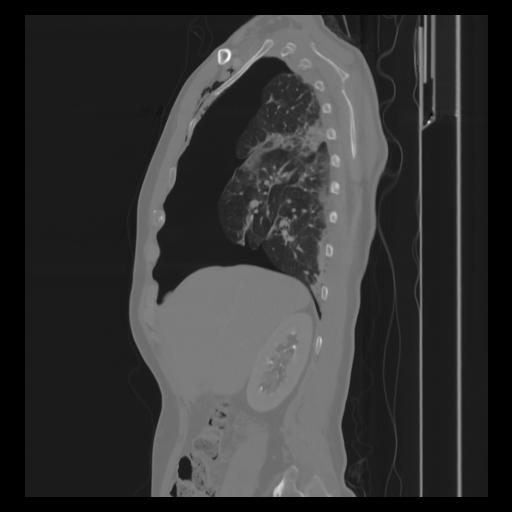

30 CUERPO,CE,Sagittal,3.000,CUERPO,Sagittal,